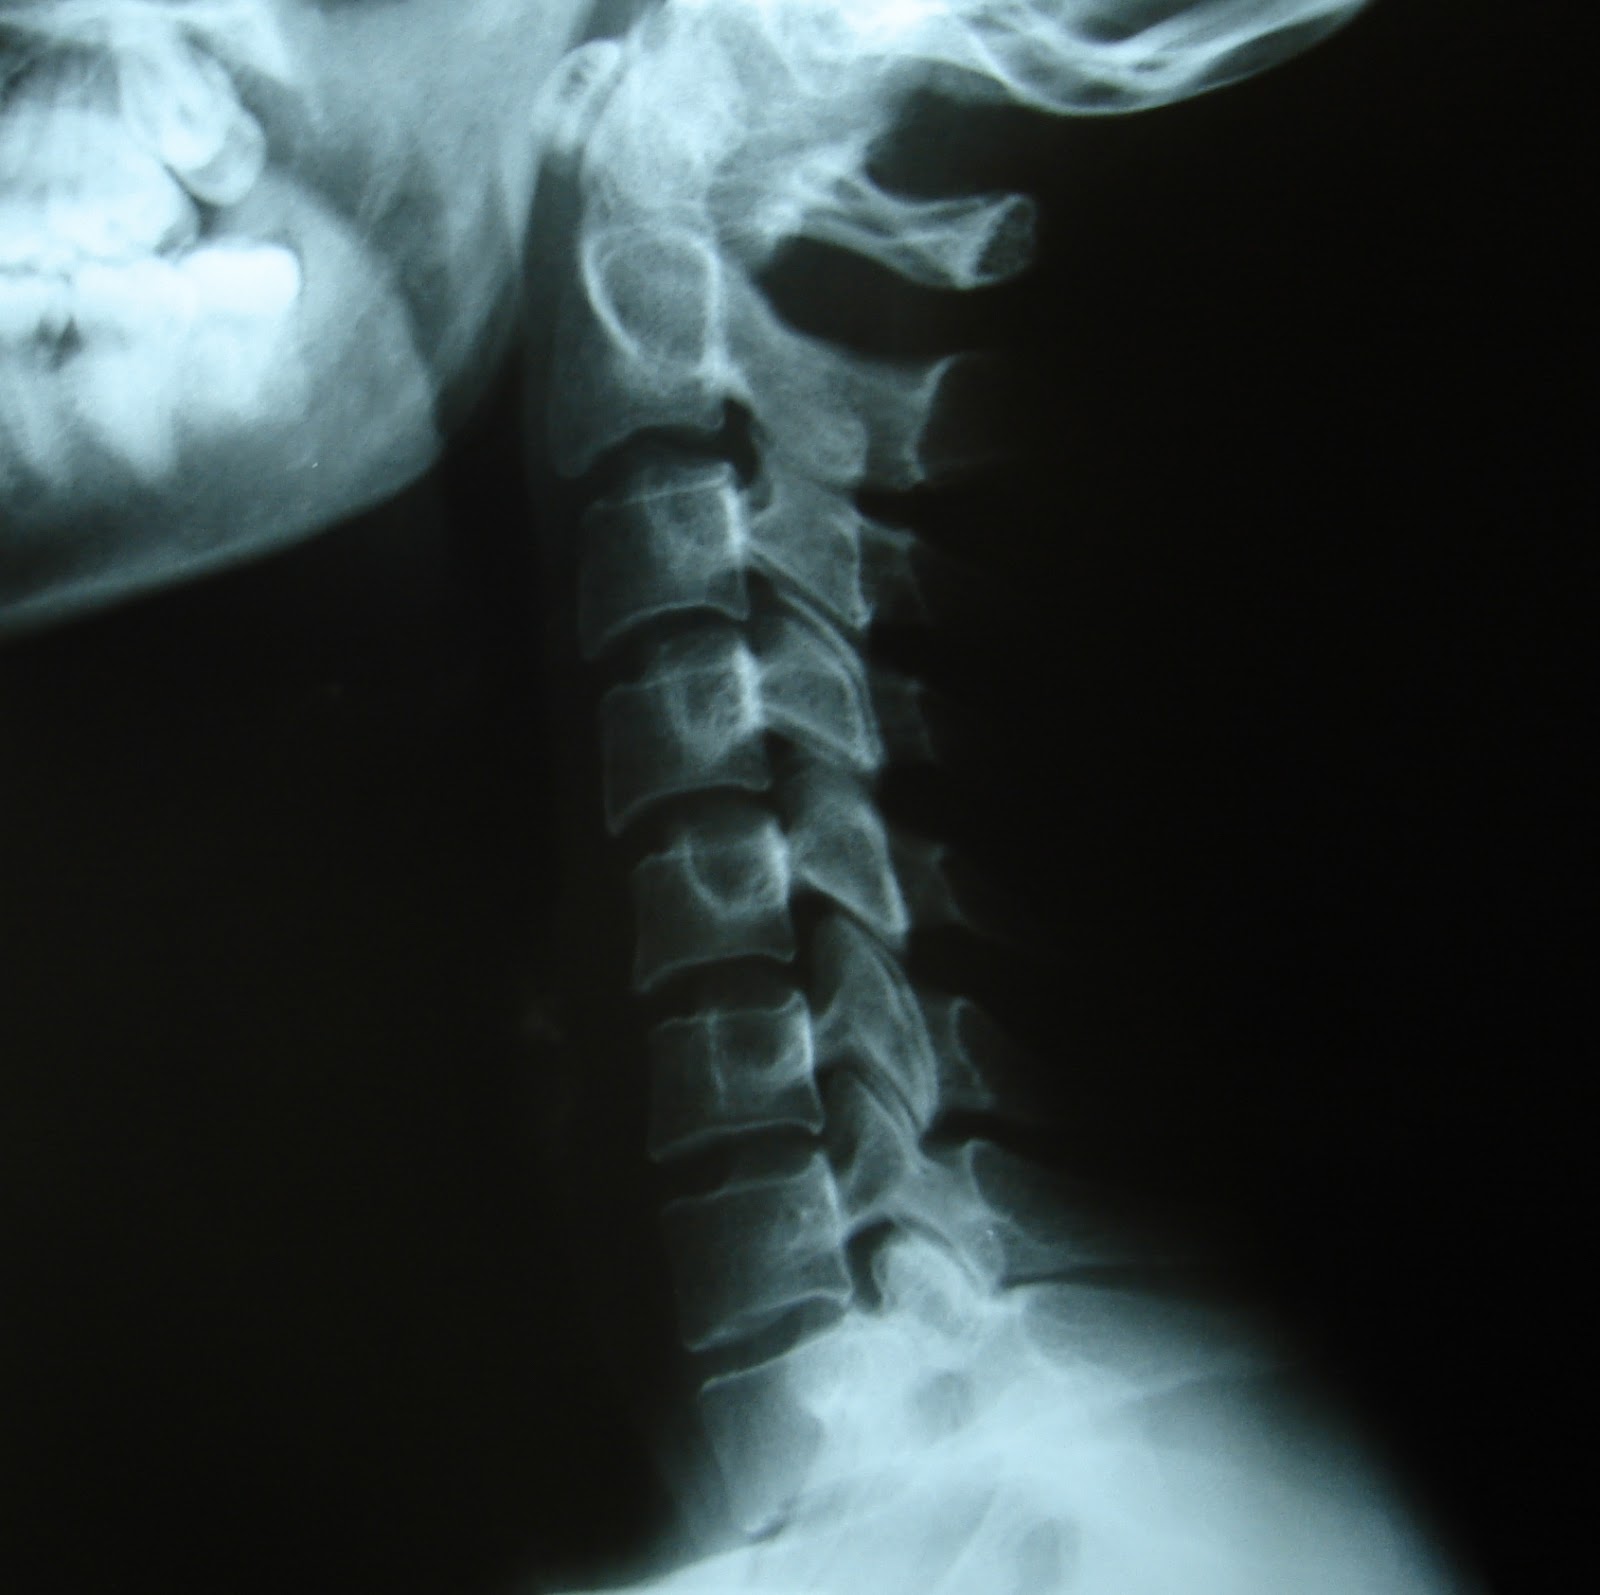

La rectificación cervical, Qué es y a qué se debe esta disfunción

WebEs recomendable recibir el tratamiento del latigazo cervical y las pautas a seguir por un profesional fisioterapeuta. En Indemnización por Accidente, le podemos recomendar. WebLo primero que debemos hacer tras sufrir un accidente de trafico es acudir al hospital, donde nos harán las pruebas y revisiones necesarias para realizar un buen diagnóstico. WebLa causa mayormente asociada a la rectificación es el latigazo cervical, generado por fuerzas rápidas de desaceleración y aceleración que generalmente ocurren durante.